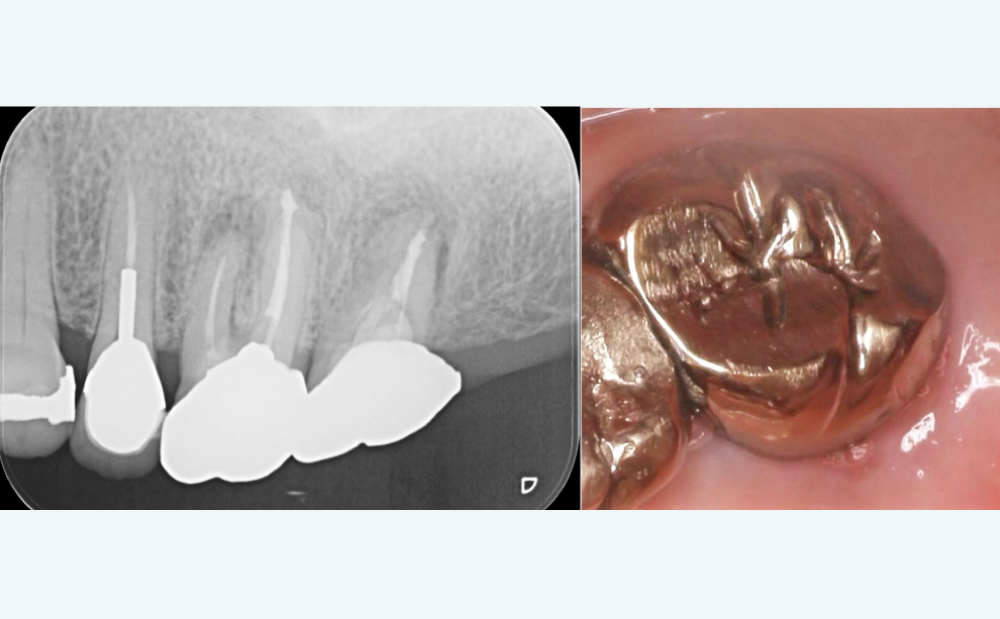

BEFORE

奥歯を抜歯し、噛みにくい

奥歯を抜歯し、噛みにくい

部分入れ歯に違和感

部分入れ歯に違和感

見た目も気になるとの相談

見た目も気になるとの相談

AFTER

自然な見た目で、噛みやすさが大幅に改善

自然な見た目で、噛みやすさが大幅に改善

「硬いものも問題なく噛めるようになった」との声

「硬いものも問題なく噛めるようになった」との声

| 治療内容 | 奥歯1本のインプラント+セラミッククラウン |

|---|---|

| 治療期間 | 約5ヶ月 |

| 費用 | 約35万円(税込) |